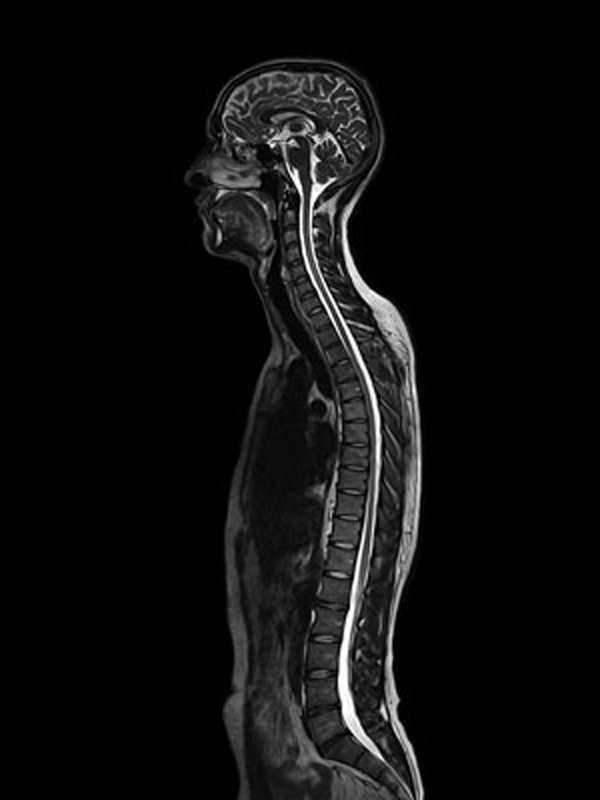

Este equipo de alta resolución integra aplicaciones únicas que permiten lograr mayor precisión en diagnóstico gracias al campo magnético de 1.5 Teslas de fuerza, de excepcional homogeneidad del campo y excelente saturación de grasa.

Utilizamos completo equipamiento de bobinas que actúan en conjunto al campo magnético del resonador, permitiendo un estudio más acabado en cada sector que se pretende explorar.

Actualmente, Resonancia Magnética Concepción ofrece bobinas dedicadas al estudio de tobillos, rodillas, piernas, columna, abdomen, muñeca y cerebro; las que permiten ofrecer la toma de imágenes para más de 30 tipos de resonancia magnética.